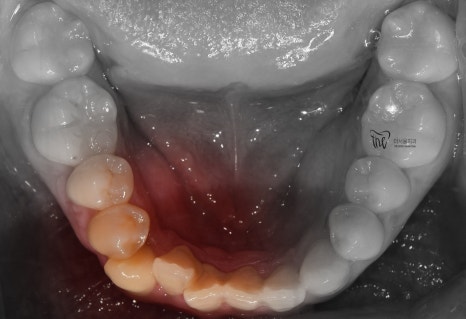

따라서, 11개월 이라는 기간이 소요되어서

치료 종료가 되었습니다.

치열이 많이 가지런하게 펴진 것을 볼 수 있고,

그간 치과에 자주 오셨기 때문에 교정유지기 를

붙여드리면서 f.u 을 자주 받으러 오셔라..

라는 안내를 드렸었습니다.

다행이였던 것은, 교정유지기 가

잘 붙어있었다는거.